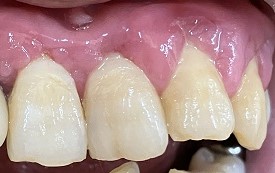

下画像2

歯肉の腫れ 初期むし歯あり(白濁)